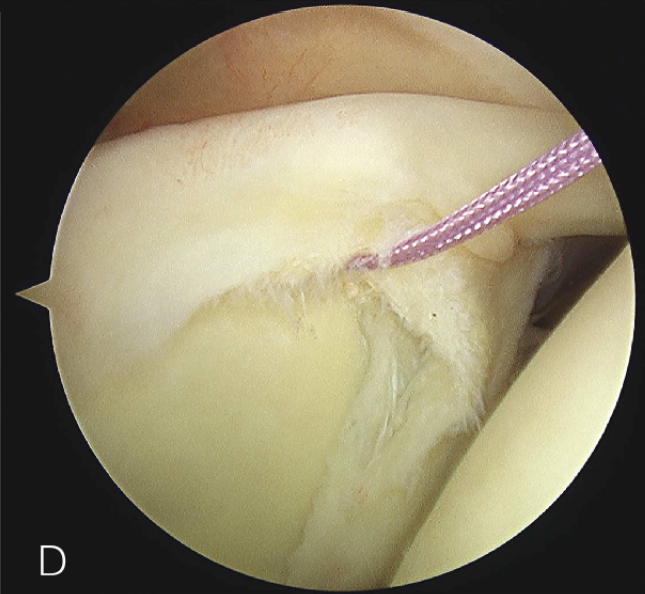

B. 应首先用腰椎穿刺针确定辅助入路的恰当位置和方向。然后在皮肤上做一个小切 A B 口,钻头导向器置入关节。

修复处准备